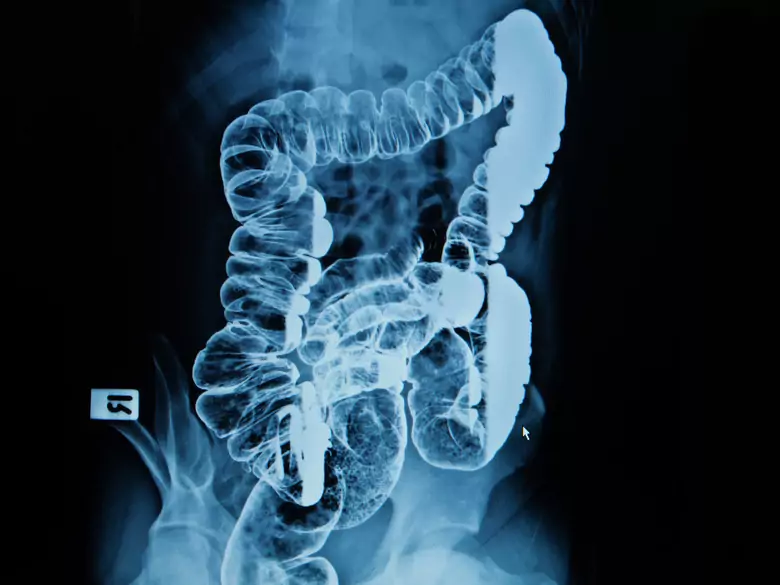

La nutrition entérale est la méthode physiologique de nutrition. Ce type de nutrition est la méthode de choix pour les patients qui ont besoin d'un soutien nutritionnel lorsqu'un régime alimentaire complet n'est pas en mesure de couvrir les besoins énergétiques.